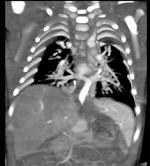

问题 女性,21岁,活动后呼吸困难,时常发生上呼吸道感染,CT扫描如图所示,请选择正确的选项 ( )

选项 A、该病人肺静脉异位引流入下腔静脉 B、该病人为心下型肺静脉异位引流 C、肺静脉异位引流根据引流肺静脉支数的不同可分为部分性及完全性 D、根据引流部位不同分为心上型、心脏型、心下型 E、考虑为肺静脉异位引流

答案 ABCDE